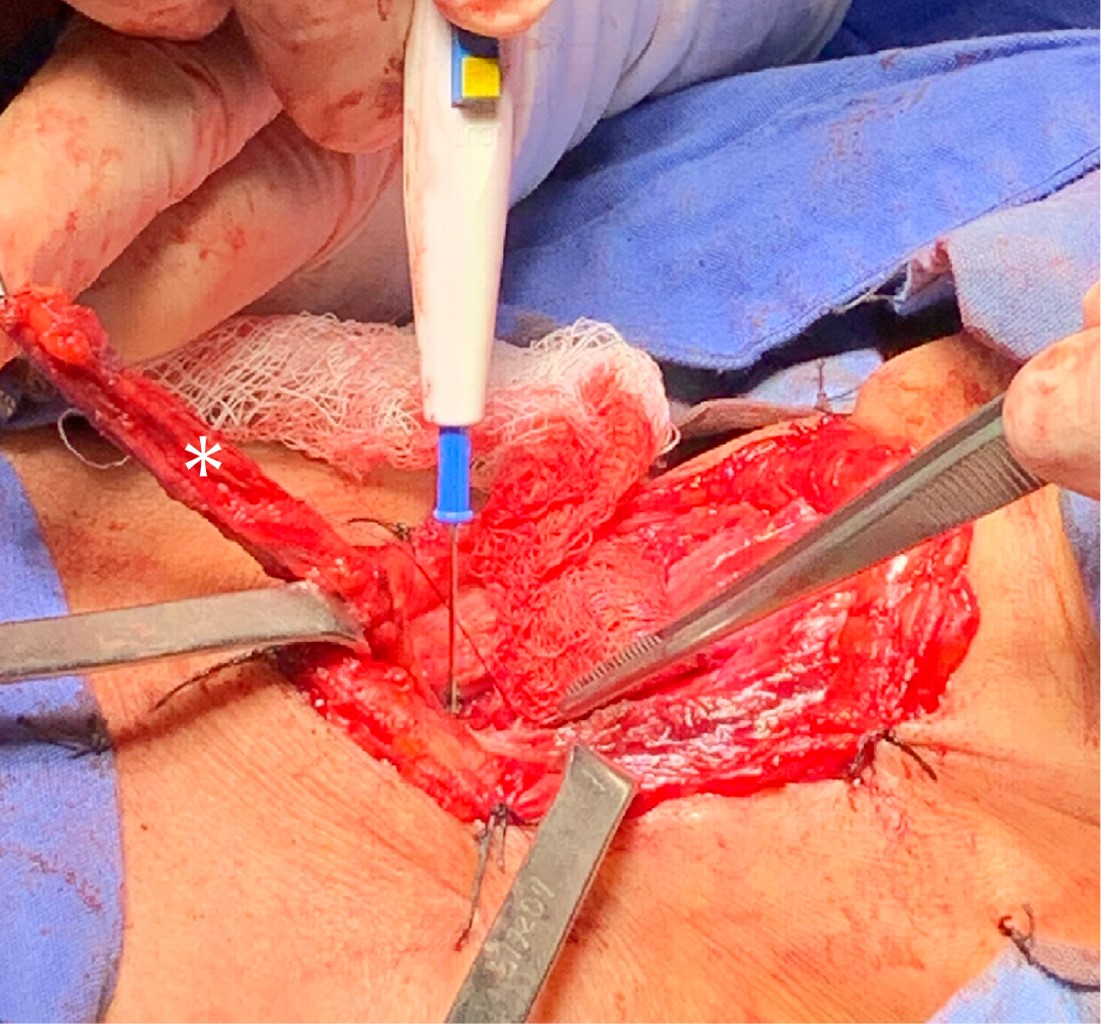

Se realizó nueva fibrobroncoscopia el 26 de abril de 2021 con hallazgo de fístula traqueoesofágica a 4 cm de cuerdas vocales de 4 cm de longitud, tráquea con 10 anillos traqueales libres a carina principal, por lo que se decidió ingresar a la paciente a nuestro instituto para manejo quirúrgico realizando cierre de fístula traqueoesofágica más cierre de estoma traqueal y colocación de traqueostomía en segundo anillo traqueal; se dejó cánula Portex 7 fenestrada sin globo. Se realizó un abordaje por cervicotomía transversal con hallazgos transoperatorios de abundantes adherencias paratraqueales y paraesofágicas, fístula traqueoesofágica de 3 cm de longitud (Figura 3). Cierre de esófago con sutura PDS 3-0 y cierre de pared posterior de tráquea con misma sutura con interposición de colgajo de músculo esternotiroideo entre ambos (Figura 4), estoma traqueal previo a nivel del cuarto anillo traqueal, el cual se recolocó a nivel de segundo anillo traqueal (Figura 5) y sangrado transoperatorio mínimo. Evolución posquirúrgica adecuada. Se realizó esofagograma de control a los siete días sin evidencia de fuga y con adecuado pase del medio de contraste (Figura 6). Se inició dieta con adecuada tolerancia y se egresó al día ocho posoperatorio sin complicaciones.

Nuestro abordaje quirúrgico fue a través de una cervicotomía transversa, ya que creemos que otorga una exposición adecuada para manipular las estructuras involucradas. El cierre de esófago y tráquea se realizó con sutura absorbible con surgete continuo en un plano de forma individual. Uno de los principios quirúrgicos de la cirugía es la interposición de un parche de músculo entre la tráquea y esófago. En nuestro caso se optó por la movilización del músculo esternotiroideo, el cual por su cercanía y longitud se adaptaba bien, sin comprometer la movilidad del cuello.